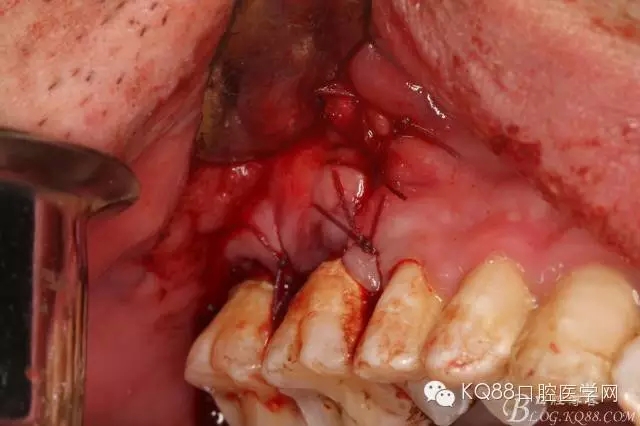

圖9.清理缺損骨腔內(nèi)的膿性分泌物及炎性肉芽組織,目的是找到18在哪里,隱約可以看到18白色的小樣子喲。

圖10.去除了覆蓋在18牙冠表面的肉芽組織,暴露出18的部分牙冠。

圖11.千辛萬苦,總算看到18的合面了,唯一難做的就是牙齒在里面打轉(zhuǎn)轉(zhuǎn),固定不住牙,也無法夾持住它,好郁悶。

圖12.沒辦法,只能往16旁邊去了點(diǎn)骨質(zhì)。才把18它呼喚出來。病人說他的嘴巴快被拉扯了。

圖13.取出18后,出現(xiàn)的巨大空腔,上頜竇粘膜完全破損。